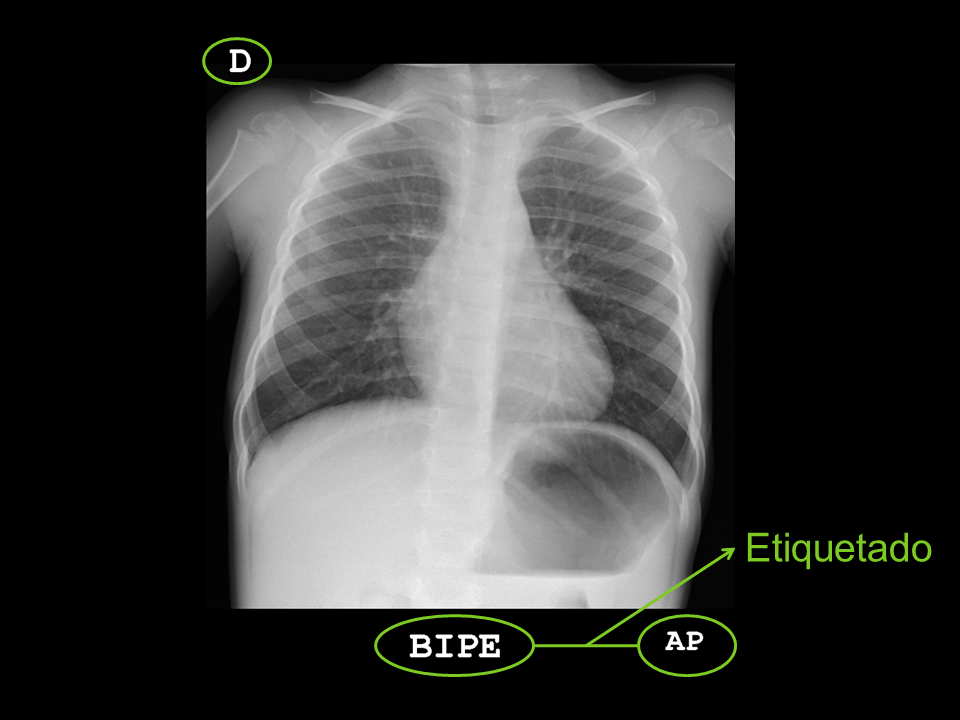

• Etiquetado de la radiografía: debe estar correctamente identificada con los datos del paciente, e incluir los datos de la proyección realizada, la posición y el marcaje del lado derecho del paciente.